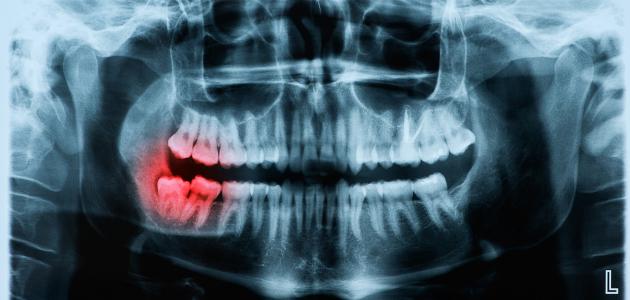

وإنّ ذلك يتطلب التوجه إلى طبيب الأسنان منذ الشعور بوجود ألم في نهاية الفك؛ للمتابعة مع طبيب الأسنان فيما يتعلق بنمو الضرس، فقد يفحص الفرد فحصًا روتنيًا وقد يشك بوجود ميل للضرس، فيطلب صور أشعة متخصصة، بناء عليها يحدد طريقة المعالجة والرعاية.

وقد يكون سبب التزاحم هو نمو عظام الفك والوجه وليس بروز ضروس العقل، ويبقى القادر على تحديد السبب الحقيقي هو طبيب الأسنان، وقد يؤدي تزاحمها لحدوث خراج بسبب الالتهابات التي تتراكم في اللثة حول ضرس العقل.

وصغر مساحة الفك في نهايته تؤدي لعدم وصول فرشاة الأسنان إليها، ممّا يؤهل لتراكم بقايا الطعام، وتكونّ الكلس والجير وربما مع مرور الوقت يؤدّي إلى التسوس، وهذا من مخاطر ضروس العقل، فقد تنتقل الالتهابات البكتيرية من ضرس العقل للرقبة أو الرأس.